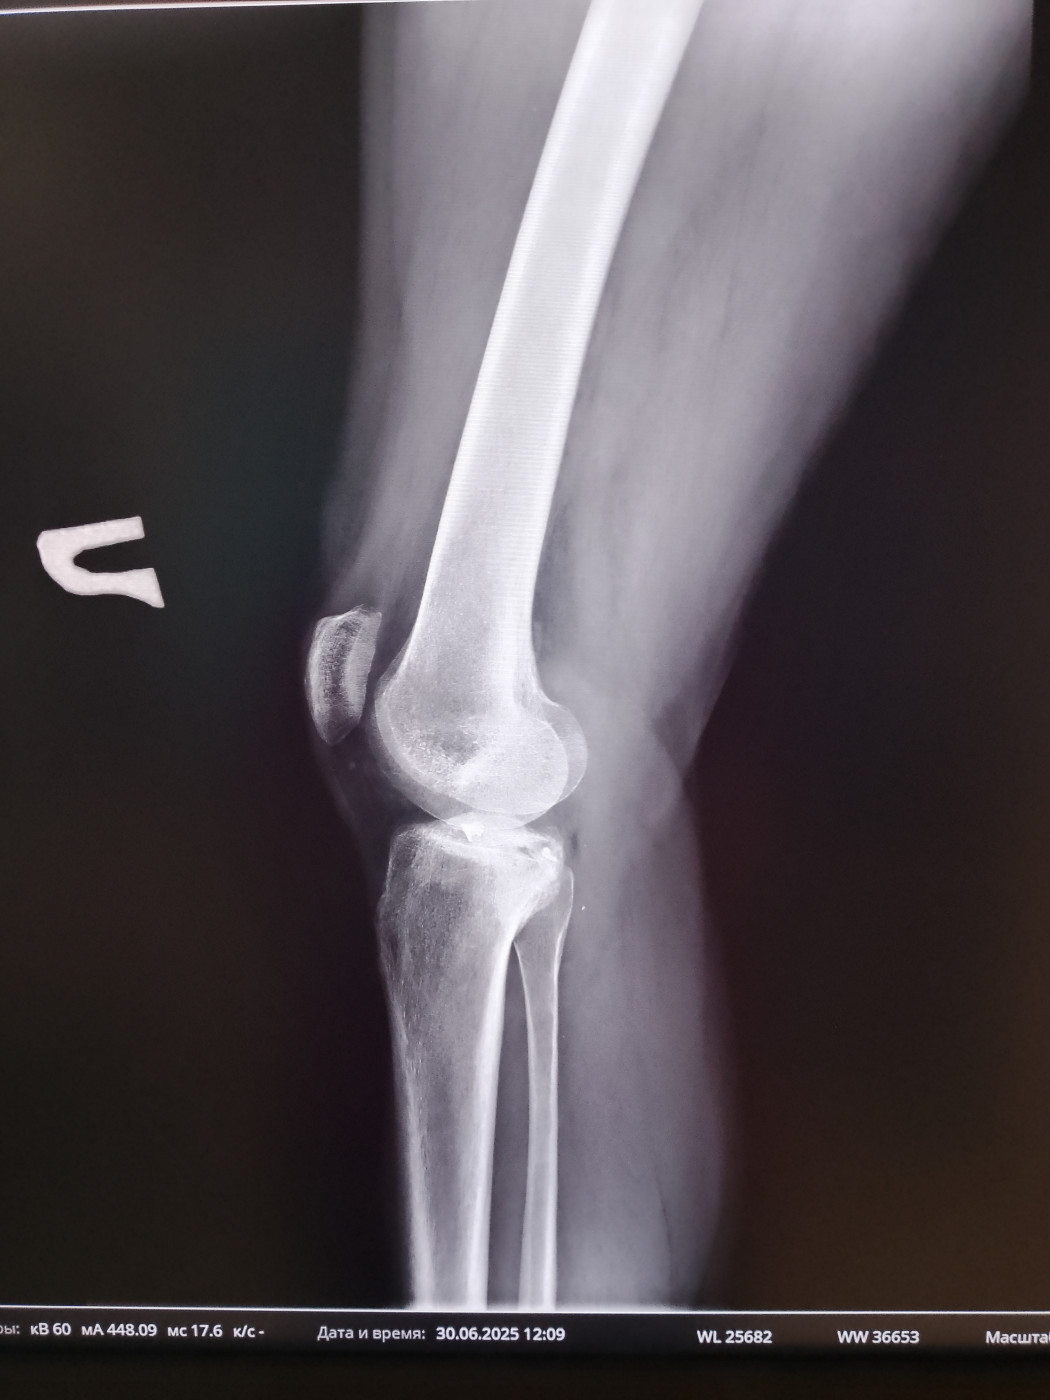

Могут ли комисовать из армии с осколками в коленном суставе